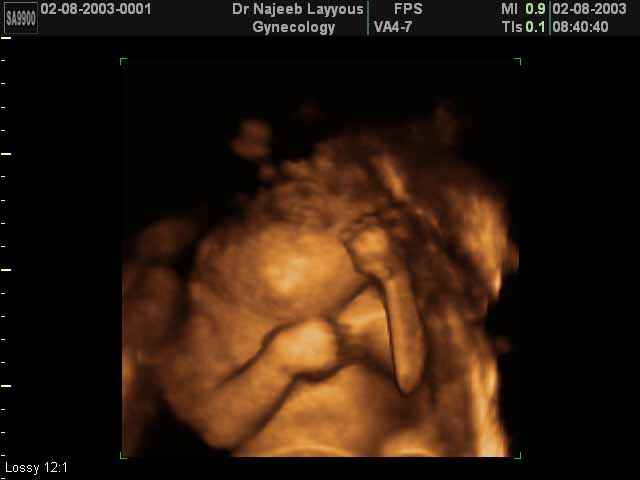

- لقطات فيديو للجنين بجهاز الموجات فوق صوتية رباعي الأبعاد

- صور لوجه الجنين في داخل الرحم

- صور لتصرفات الجنين داخل الرحم